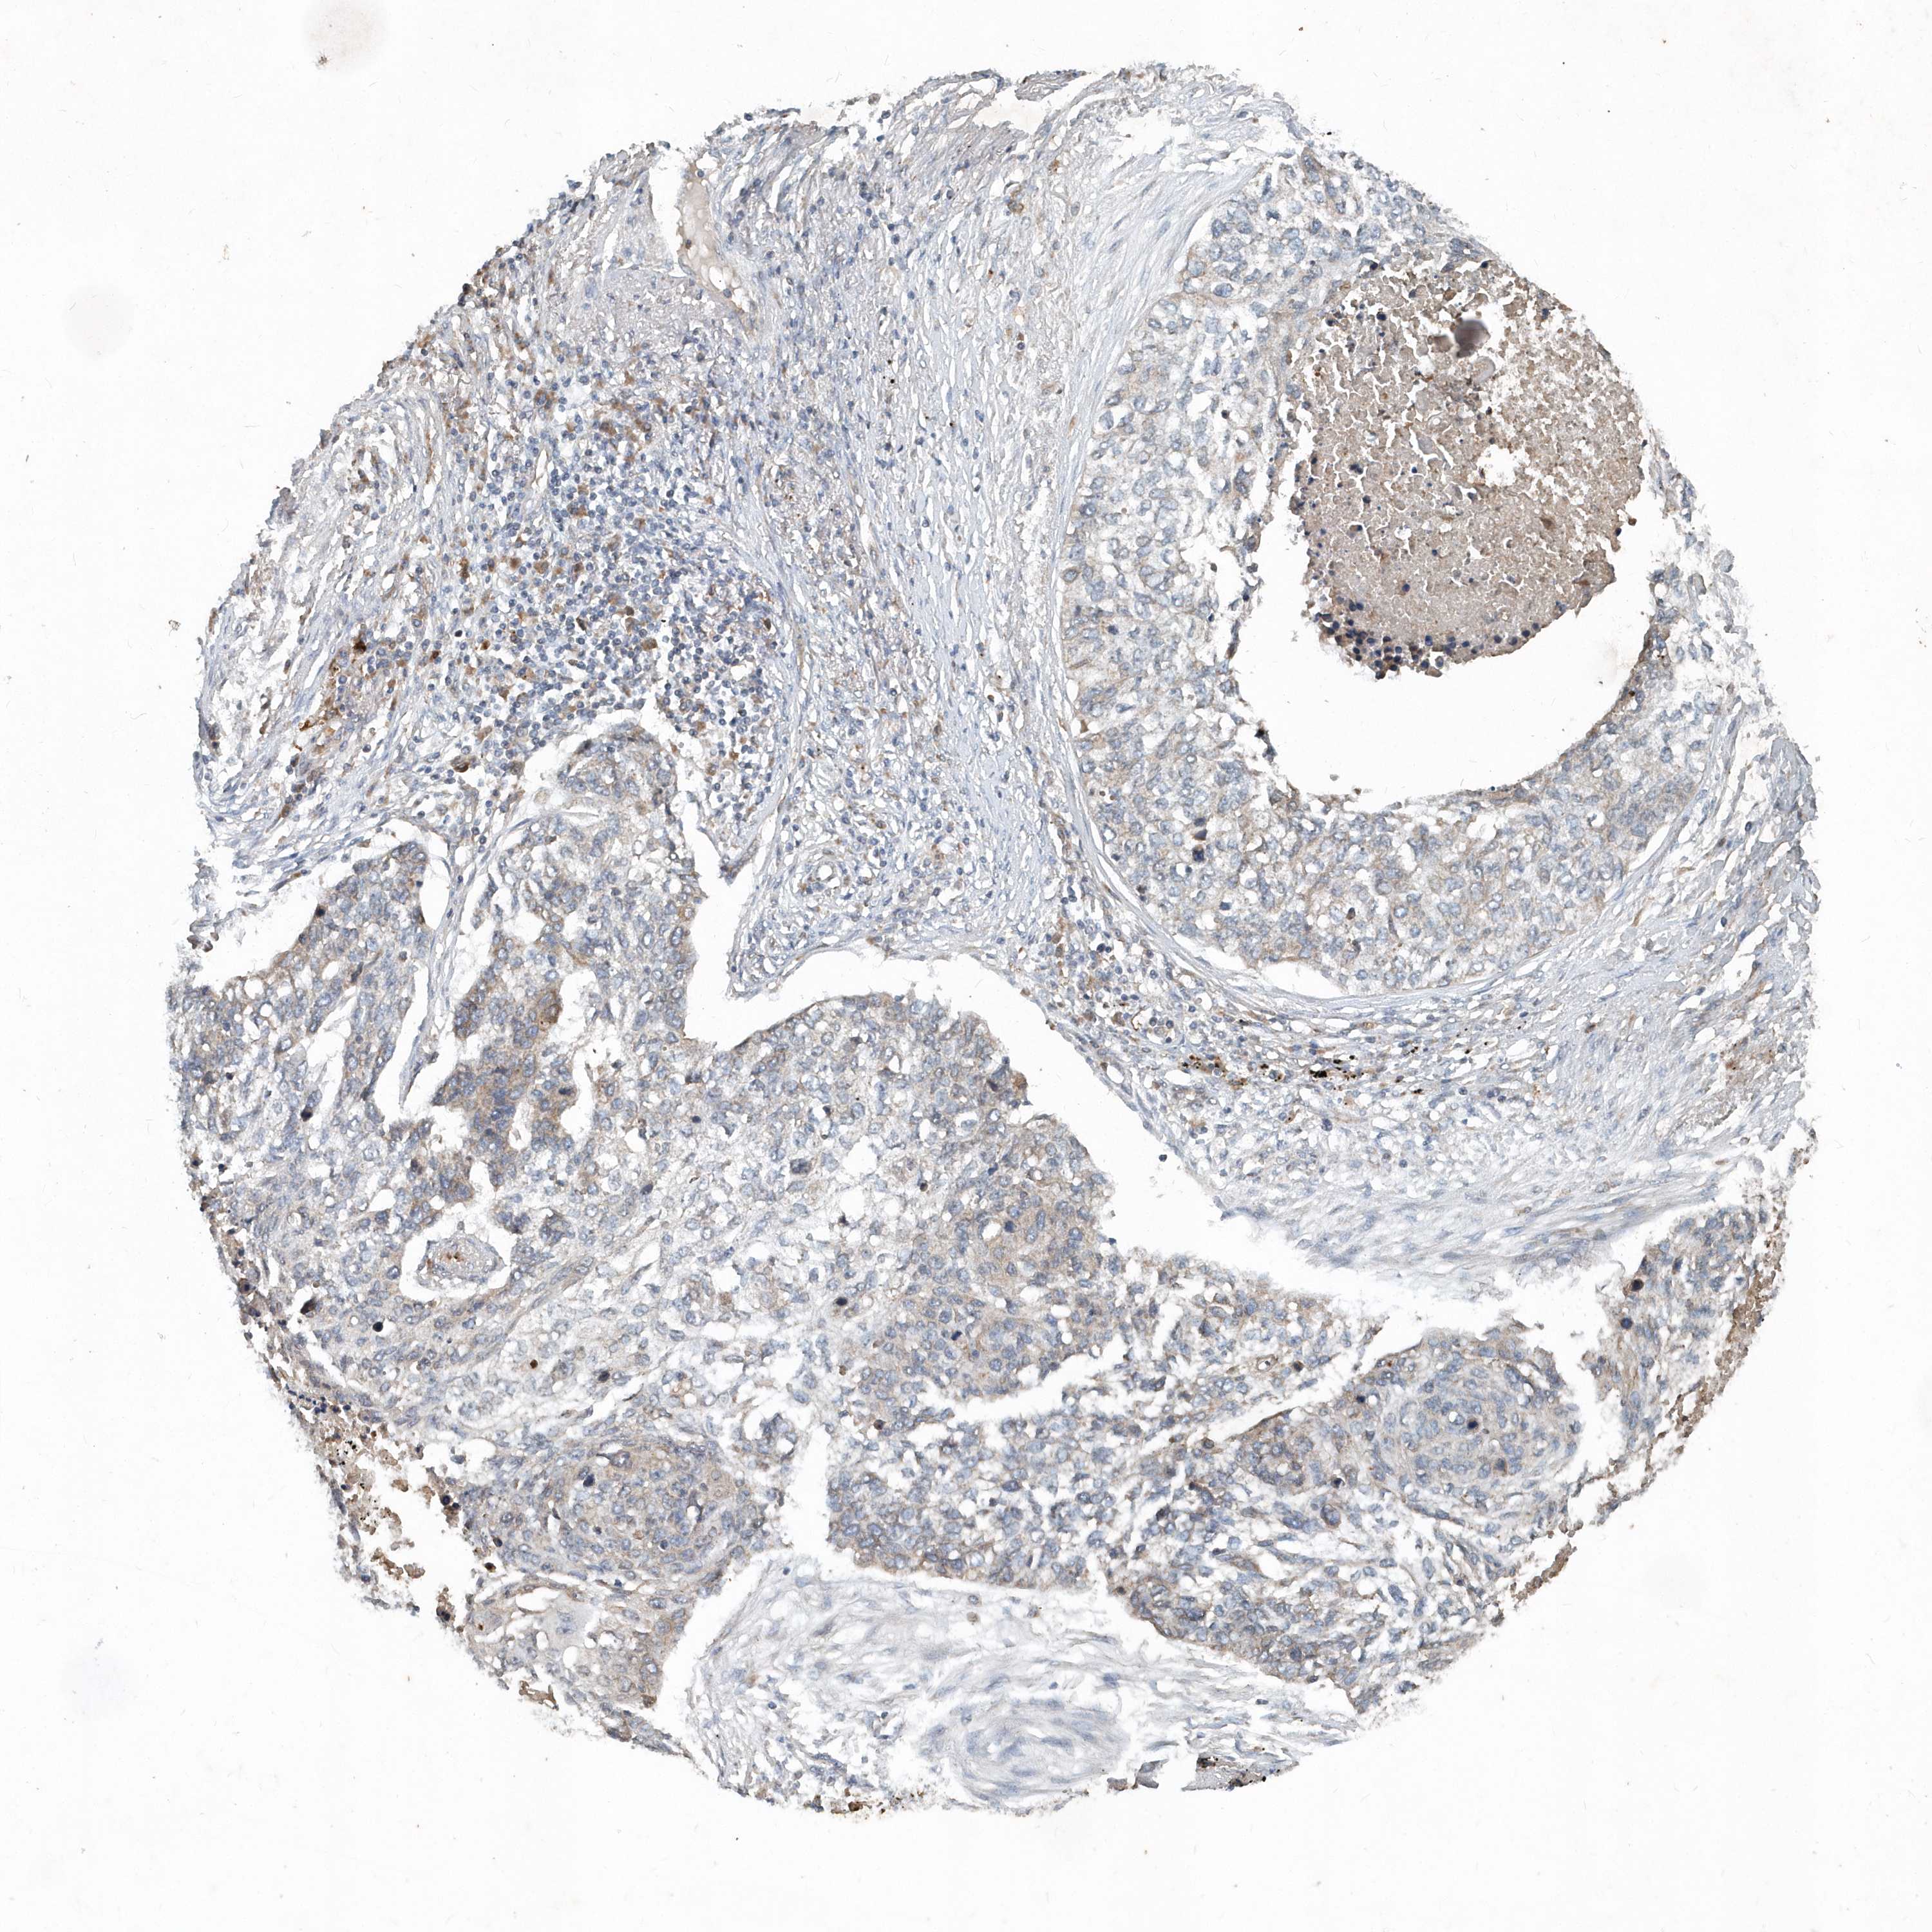

CANCER LUNG CANCER Show tissue menu

LUAD TCGA LUAD VALIDATION LUSC TCGA LUSC VALIDATION PROTEIN LUAD CPTAC PROTEIN LUSC CPTAC PROTEIN EXPRESSION